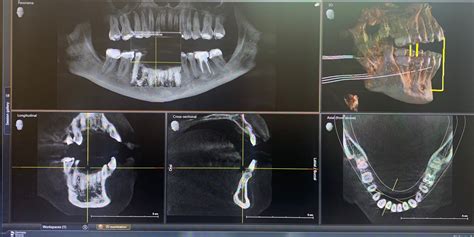

Las máquinas de rayos X dentales son ampliamente utilizadas en odontología. El equipo está diseñado para la pronta recuperación de imágenes de pacientes con dientes, tanto para el diagnóstico y diagnóstico, como en el proceso de procedimientos terapéuticos e intervención quirúrgica. La industria dental está en constante desarrollo y se caracteriza por una serie de tendencias pronunciadas. Uno de ellos es el funcionamiento de los sistemas de visualización en el proceso de proporcionar una atención médica eficaz a los pacientes.

El sistema de visualización es un equipo de diagnóstico médico eficaz. Permite a los dentistas identificar con precisión los problemas y las enfermedades, llevar a cabo con seguridad las manipulaciones y los procedimientos de tratamiento. Estos son "instrumentos de confianza" originales entre el dentista y su cliente. Con la ayuda de escáneres y cámaras de video, el dentista puede demostrar visualmente al paciente el problema que necesita tratamiento. Otra ventaja de los sistemas de visualización es que proporcionan la información más completa en el proceso de trabajo.

- Radiovisiógrafos digitales: Son más caros, pero al instante forman una imagen con buenos detalles. Preste atención a los equipos que soportan el trabajo con el radiovisiógrafo y la sincronización con el ordenador.